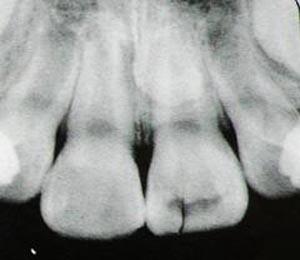

9岁儿童冠折,下唇组织挫伤

牙折线延伸至牙槽骨,诊断为冠-根

对合作的患儿,有条件时,首先是作X线检查,了解外伤牙的损伤程度、牙根发育状况、外伤乳牙与恒牙胚的关系等,为制定恰当的治疗方案提供依据。对于年龄较小,无法拍摄X线片的患儿,需根据临床检查结果制定合适的治疗计划,但要告知家长必须作定期的复查,必要时再行X线检查。